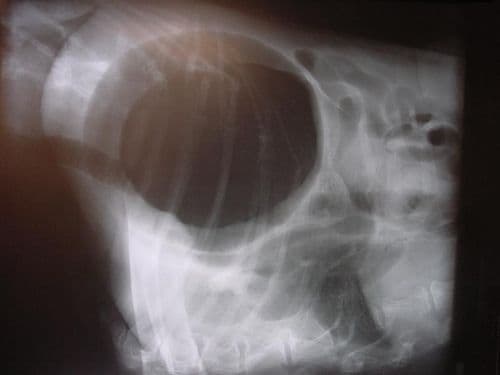

A gyomorcsavarodás